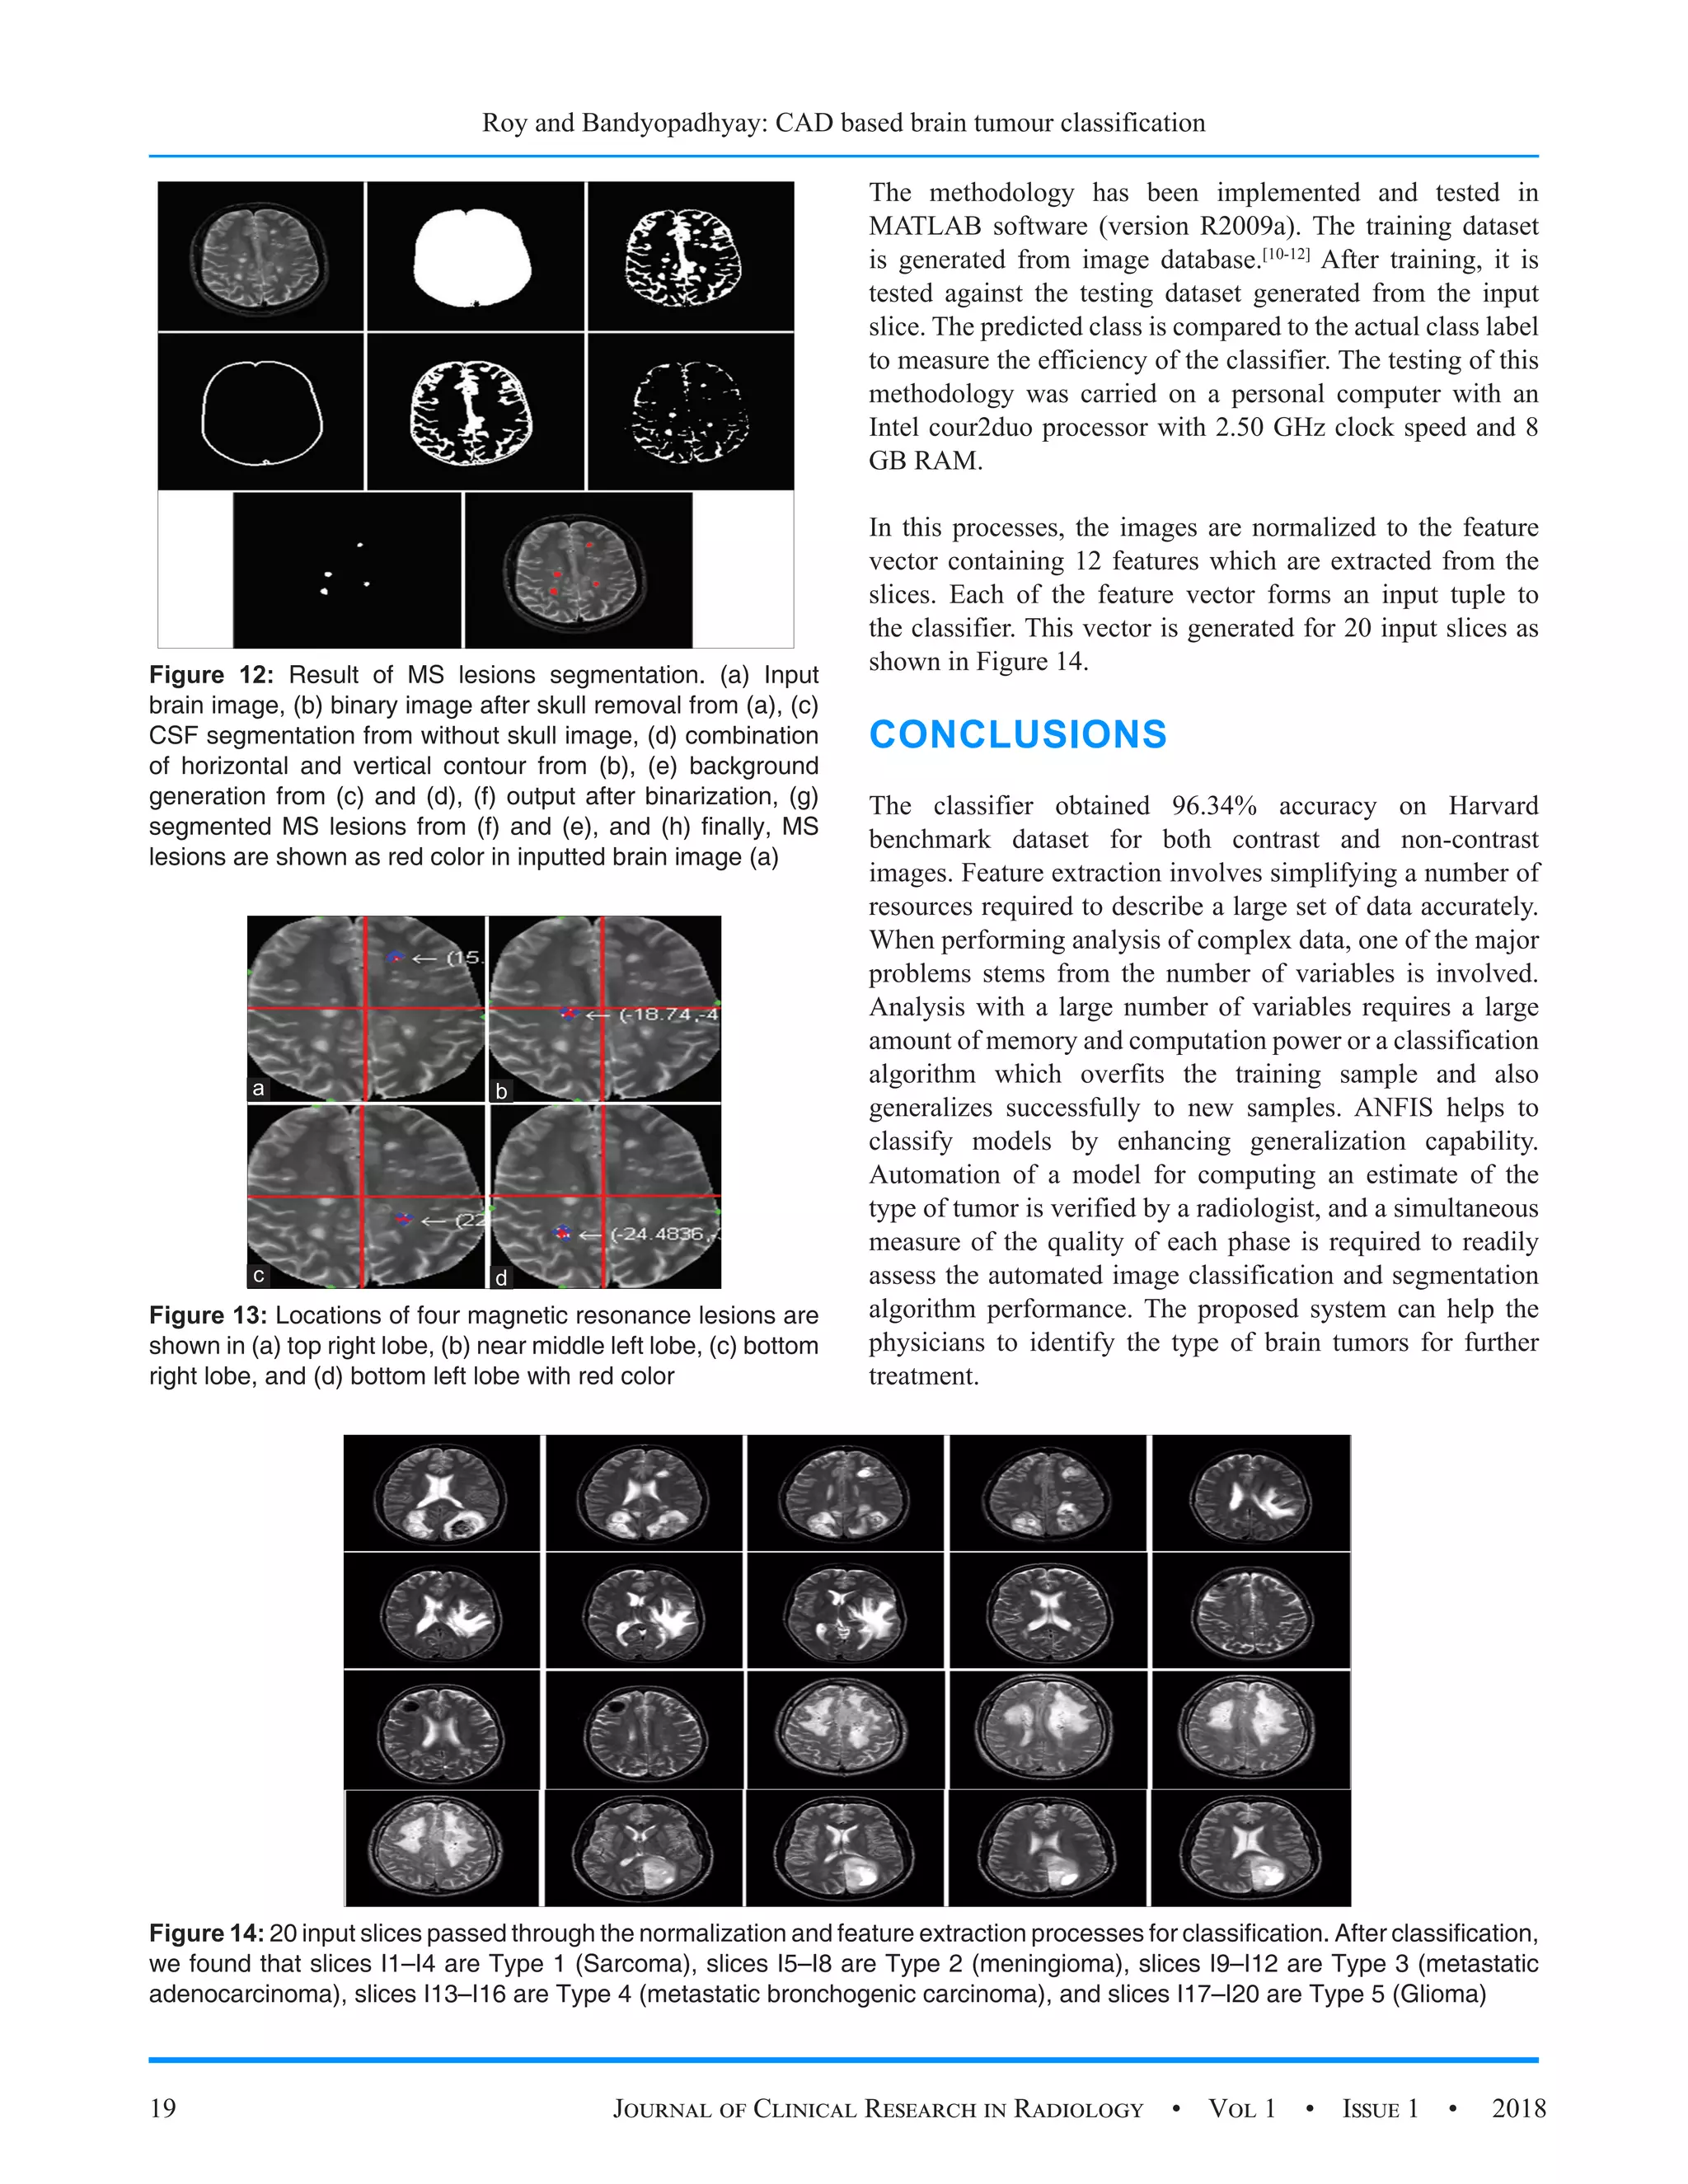

Figure 12: Result of MS lesions segmentation. (a) Input

brain image, (b) binary image after skull removal from (a), (c)

CSF segmentation from without skull image, (d) combination

of horizontal and vertical contour from (b), (e) background

generation from (c) and (d), (f) output after binarization, (g)

segmented MS lesions from (f) and (e), and (h) finally, MS

lesions are shown as red color in inputted brain image (a)

Figure 14: 20 input slices passed through the normalization and feature extraction processes for classification. After classification,

we found that slices I1–I4 are Type 1 (Sarcoma), slices I5–I8 are Type 2 (meningioma), slices I9–I12 are Type 3 (metastatic

adenocarcinoma), slices I13–I16 are Type 4 (metastatic bronchogenic carcinoma), and slices I17–I20 are Type 5 (Glioma)

Figure 13: Locations of four magnetic resonance lesions are

shown in (a) top right lobe, (b) near middle left lobe, (c) bottom

right lobe, and (d) bottom left lobe with red color

The methodology has been implemented and tested in

MATLAB software (version R2009a). The training dataset

is generated from image database.[10-12]

After training, it is

tested against the testing dataset generated from the input

slice. The predicted class is compared to the actual class label

to measure the efficiency of the classifier. The testing of this

methodology was carried on a personal computer with an

Intel cour2duo processor with 2.50 GHz clock speed and 8

GB RAM.

In this processes, the images are normalized to the feature

vector containing 12 features which are extracted from the

slices. Each of the feature vector forms an input tuple to

the classifier. This vector is generated for 20 input slices as

shown in Figure 14.

The classifier obtained 96.34% accuracy on Harvard

benchmark dataset for both contrast and non-contrast